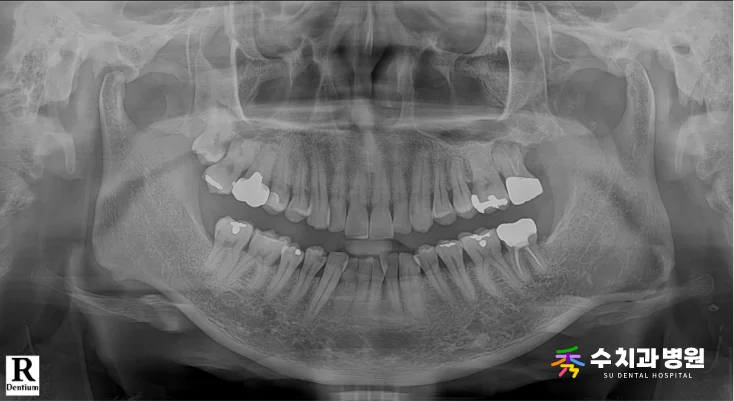

[📸 치료 전 엑스레이사진] (촬영일: 2025년 9월)

정밀 검진과 방사선 사진을 꼼꼼히 확인해 보니,

보철물이 빠진 치아 바로 뒤쪽 어금니에도

새로운 충치가 추가로 관찰된 상태였습니다.